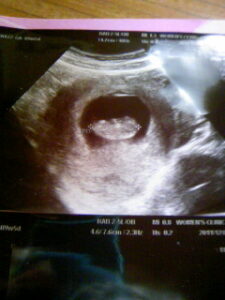

左はトコちゃんベルト着用前(7㎝の骨盤のゆるみ)⇒右は着用後(2㎝の骨盤のゆるみ) 流産歴が数度あり、今回の妊娠後も出血など不安定で来院。

左の写真で骨盤のゆるみが7㎝以上あり、子宮内の胎嚢の形状が悪いので、トコちゃんベルトを正しく着用を指導しました。 着用後は右の写真、丸くふっくらとした子宮内の胎嚢の写真になりました。(2㎝の骨盤のゆるみ) その後無事に出産されました。喜びの手紙を頂きました。